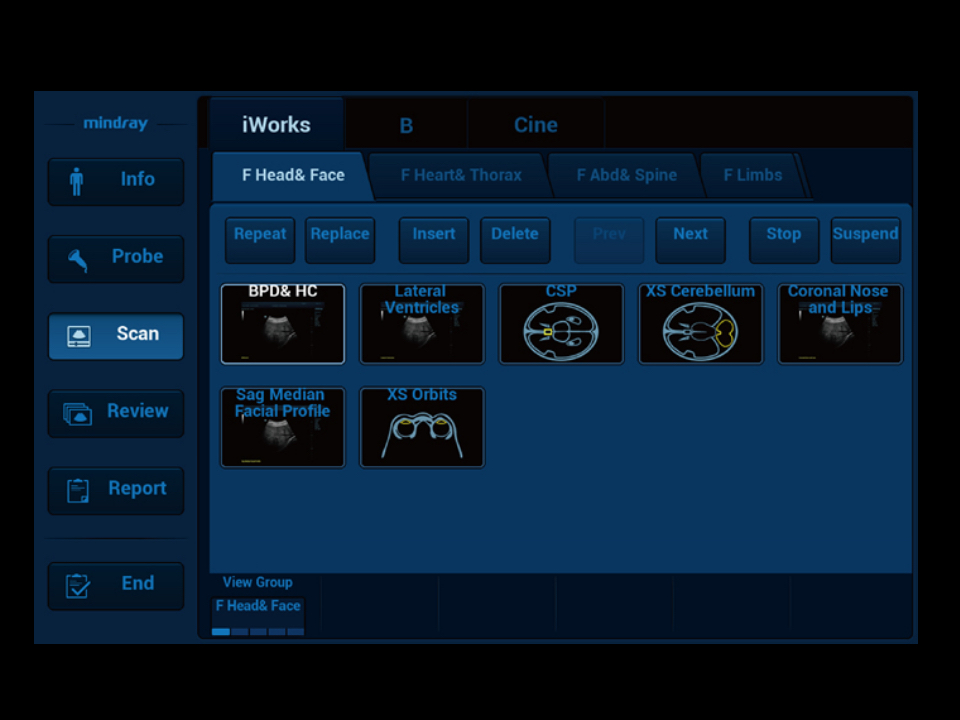

Thanks to the innovative, software-driven ZST+ platform, the Resona series is continuously evolving with the leading-edge technologies to meet the most challenging diagnostic demands in womenŌĆÖs health practice. More importantly, it is designed with the understanding that the wisdom of experts is always precious, and you need more intelligent partner for enhanced speed and confidence. Finally, Resona series with Zone Intelligence provides a total solution to help you with diagnostic confidence, efficiency, and standardization across different diagnostic challenges in todayŌĆÖs demanding and overburden hospital environment.